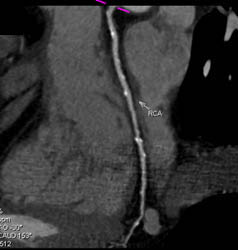

LAD Stenosis